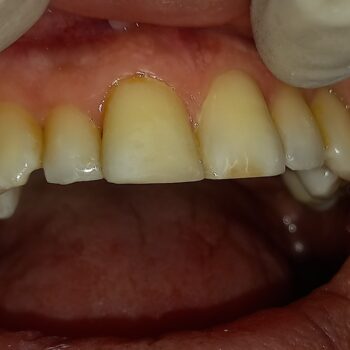

Η σημασία της προσωρινής αποκατάστασης κατά τη διάρκεια προσθετικής εργασίας